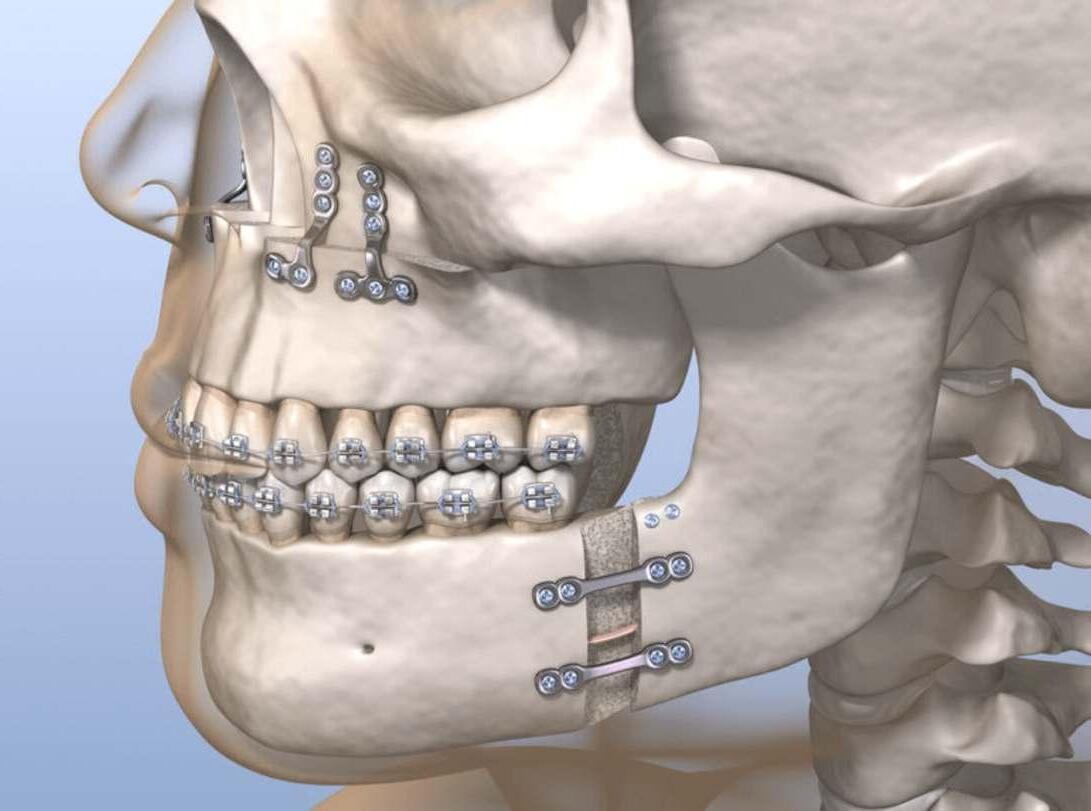

• Corrección de Maxilares (cirugía ortognática)

• Implantes dentales

• Cirugía terceros molares

• Trauma facial

• Patologías de maxilares